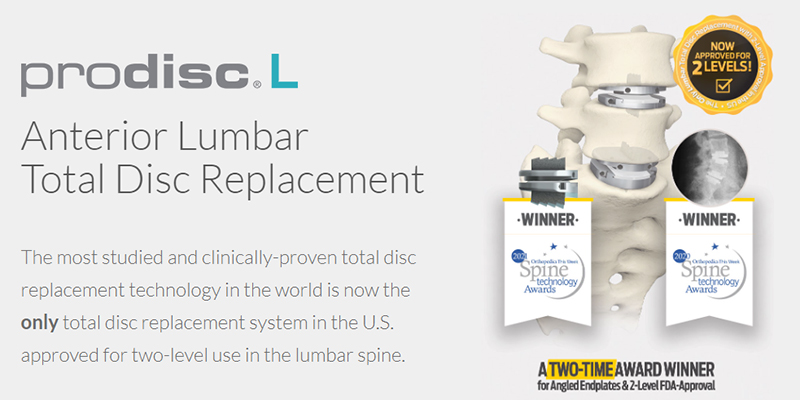

Prodisc® is a Total Disc Replacement (TDR) technology platform that offers a surgical treatment proven to maintain spinal balance and motion, decelerate adjacent level reoperations, and accelerate the return to normal activities.

Centinel Spine is currently the only company in the United States to offer Total Disc Replacement devices for both the cervical and lumbar artificial disc replacement. It is the only total disc replacement system in the U.S. approved for two-level use in the lumbar spine.

The prodisc L Total Disc Replacement has been determined to be safe and effective in the treatment of degenerative disc disease (DDD) at two levels from L3 to S1.

The 1st implantation of a prodisc L took place in 1990, and the 2nd generation design received US PMA approval in 2006.

With such a lengthy clinical history and global usage, the prodisc line of total disc replacements are the most widely studied TDRs in the world.

prodisc design has been validated with over 225,000 device implantations worldwide1 and more than 540 published papers2

The only total disc replacement system in the U.S. approved for two-level use in the lumbar spine

More than 225,000 device implantations and a reported reoperation rate of less than 1%